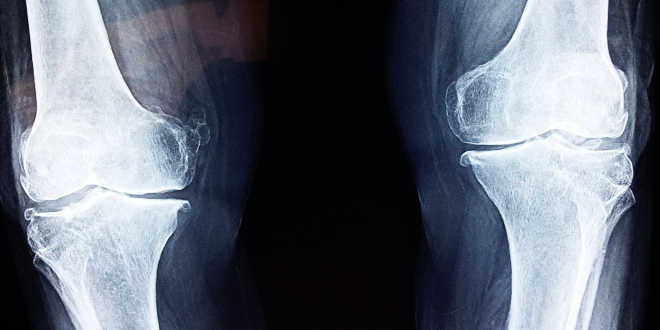

Arthrosis happens when a joint cartilage is damaged. Cartilages are in charge of producing a buffering effect between the joints. However, damaged cartilage is unable to do so. Therefore, one bone rubs against another one, causing discomfort, inflammation and problems to move. This is when glucosamine comes into play.

It regenerates the cartilaginous tissue, tendons, and other connective tissues of the body. Then, it builds these materials and inhibits the enzymes that destroy the cartilage, particularly fighting against arthrosis. The body can develop arthrosis when it does not get enough glucosamine. This degenerative disease that affects millions of people around the world, produces a collapse of the joint “buffers”, specially those that support the body weight, like the hips or knees.

After five years of studies, tests and analysis, the “GAIT” (Glucosamine/Chondroitin Arthritis Intervention Trial) research reported that the combination of glucosamine and chondroitin is more effective than medications when treating moderate or severe knee discomfort due to osteoarthrosis.

- This dietary supplement can help to treat glaucoma, osteoarthritis, back and joint pain. Most studies on glucosamine have been conducted on patients with knee osteoarthritis.